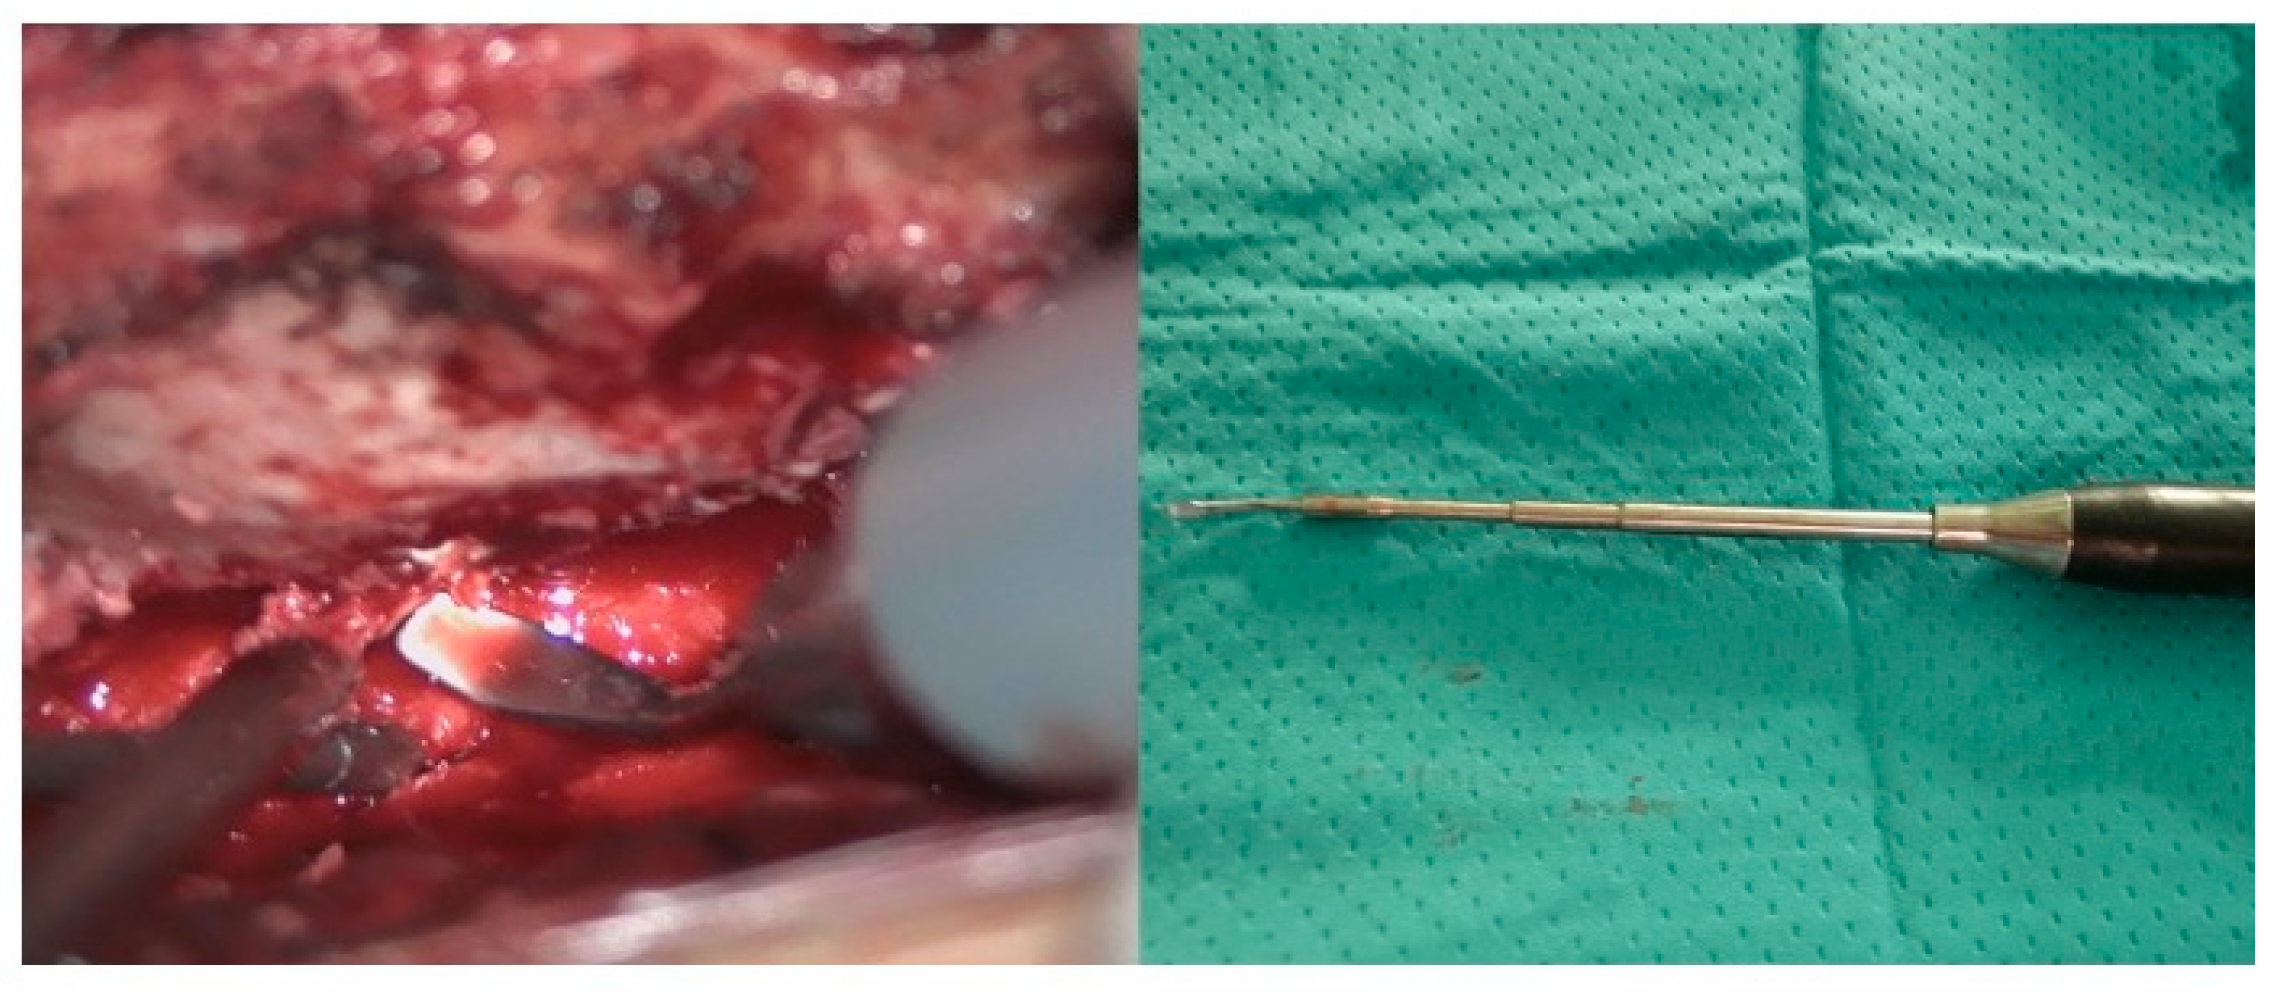

Figure 2.

Piezoelectric osteotome while performing laminoplasty (left) and intra-operative view of a long tip used to reach deep surgical fields.